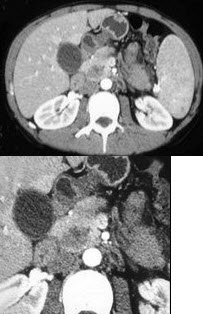

女,56岁,腹部胀痛不适、食欲减退,影像表现如下图,最佳诊断是( )

A:急性胰腺炎

B:慢性胰腺炎

C:胰腺腺癌

D:胰腺转移癌

E:胰腺假性囊肿